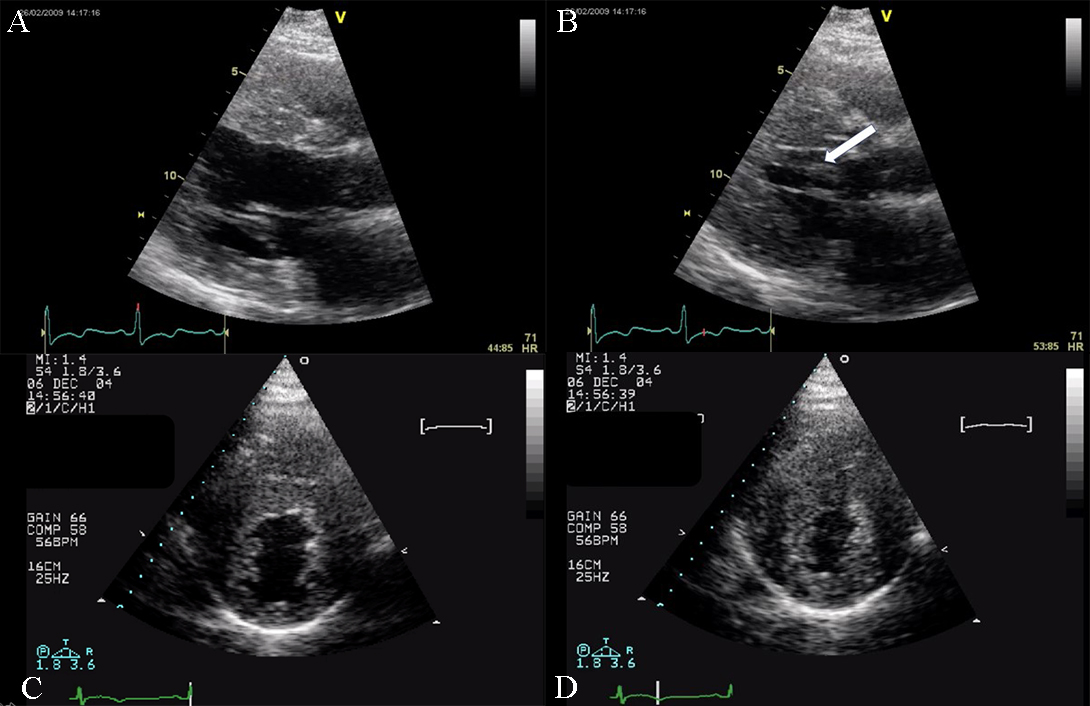

Fig. 5.Echocardiographic aspect of HCM. (A) Parasternal long-axis view diastolic frame showing increased thickness of septum and inferolateral wall. (B) Parasternal long-axis view systolic frame showing (arrow) systolic anterior motion of the anterior mitral valve. (C) Short axis view diastolic frame showing significant left ventricular hypertrophy. (D) Short axis view systolic frame showing reduced left ventricular end-systolic diameter.